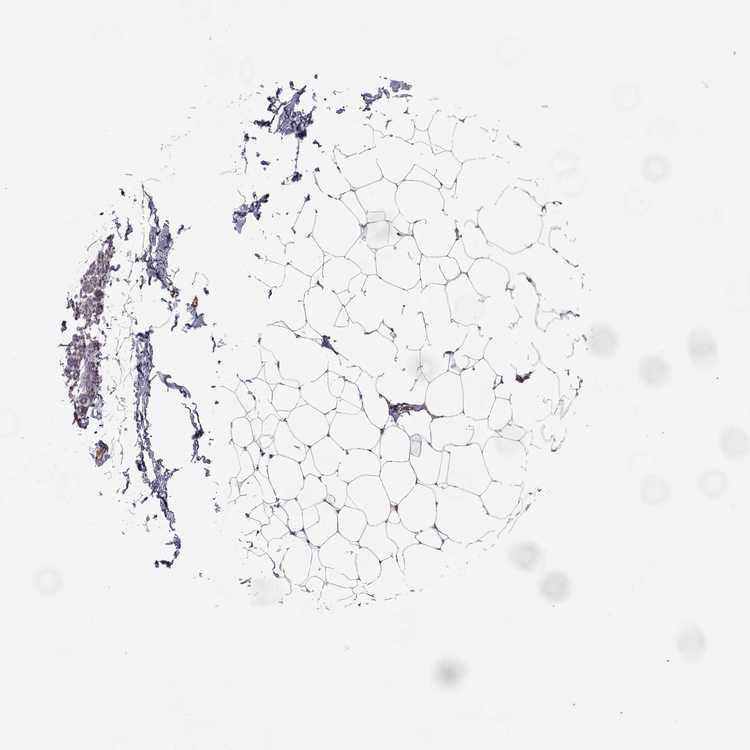

BREAST - Antibody stainingi

Antibody staining in the annotated cell types in the current human tissue is reported as not detected, low, medium, or high, based on conventional immunohistochemistry profiling in selected tissues. This score is based on the combination of the staining intensity and fraction of stained cells.

Each image is clickable and will lead to virtual microscopy that enables deeper exploration of all samples and also displays staining intensity scores, fraction scores and subcellular localization as well as patient and tissue information for each sample.

Antibody HPA008427

Adipocytes Medium

Glandular cells Low

Myoepithelial cells Low